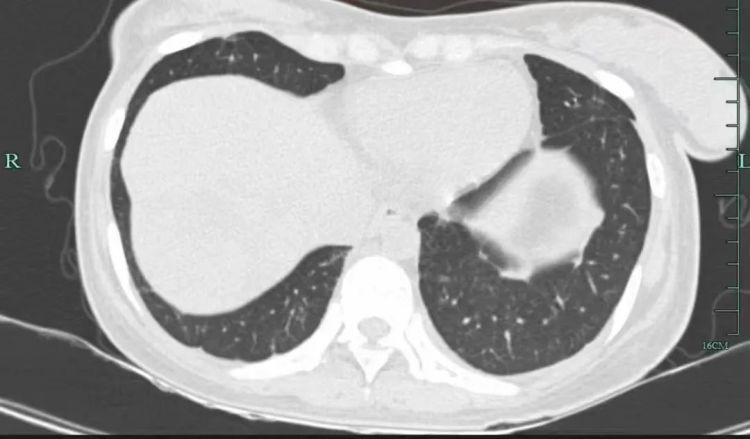

治疗后

几个月后,她的病情逐渐好转,肺部的“满天星”也消失了!小谢满心感激:“是丁主任救了我的命,让我重获新生!”